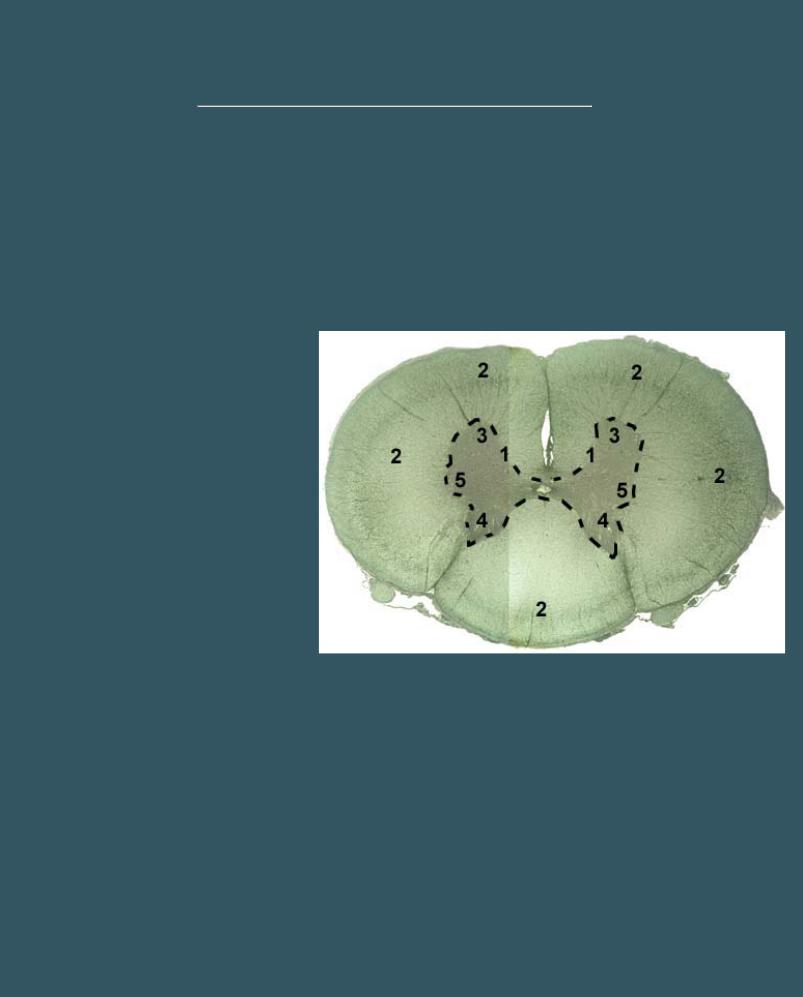

СПИННОЙ МОЗГ

Импрегнация нитратом серебра

1 - серое вещество

2 - белое вещество

3 - передние рога серого вещества

4 - задние рога серого вещества

5 - боковые рога серого вещества